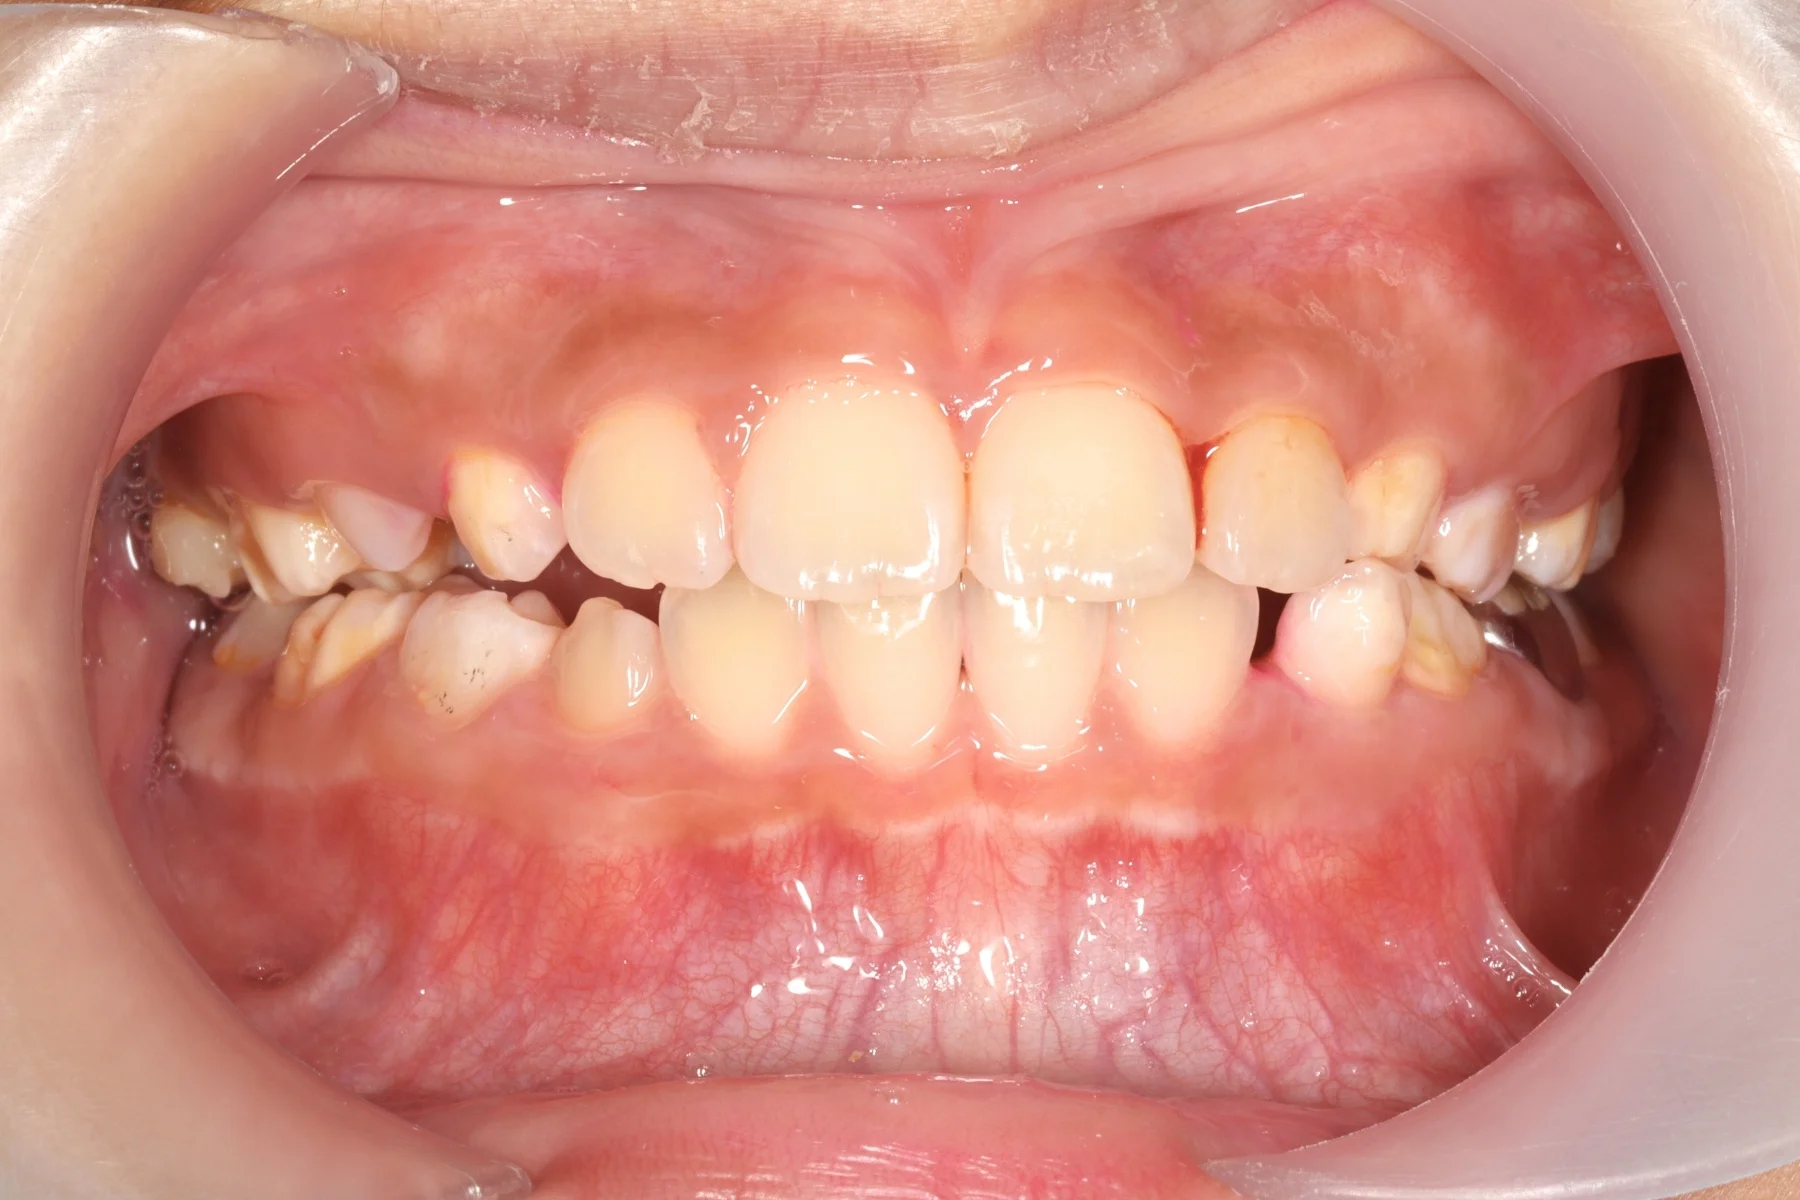

兒童隱適美_術前

兒童隱適美_術後